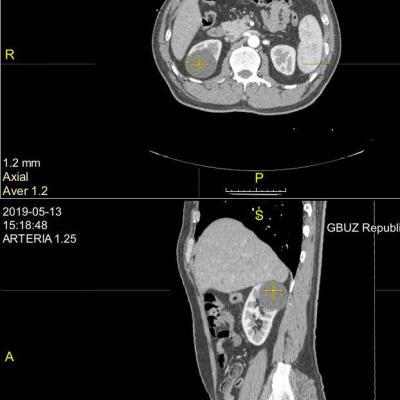

В конце прошлого года проходил УЗИ, там и обнаружилось новообразование, послали к урологу, потом в МОНИКИ к урологу, потом на КТ. В результате 16го февраля поставили диагноз - рак левой почки. Размер примерно 45мм. В понедельник 19 февраля были на приёме в МООД в Балашихе. Там подтвердили диагноз, и приговорили к удалению почки. На вопрос - можно ли сделать лапароскопическую операцию, нам ответили, что у него в брюшной полости скорее всего полно спаек (из-за перенесённого перитонита). Поэтому будут делать полноценную операцию, с доступом через забрюшинную полость. И удалять почку целиком, или возможно часть оставить, будут решать в процессе операции. Пока собираем анализы, консультируемся с кем можем, и ждём радиоизотопное исследование (назначено на 5 марта).

Ещё один момент - на второй почке киста 2,3см. Получается если одну почку удалят, вторая тоже не совсем здоровая.

Прилагаю сканы описаний УЗИ, КТ, выписку из приёма у местного уролога, анализ крови на ПСА, направление на радиоисследование в Балашихе. Есть ещё сам снимок КТ, но он на плёнке, отсканировать не получается.